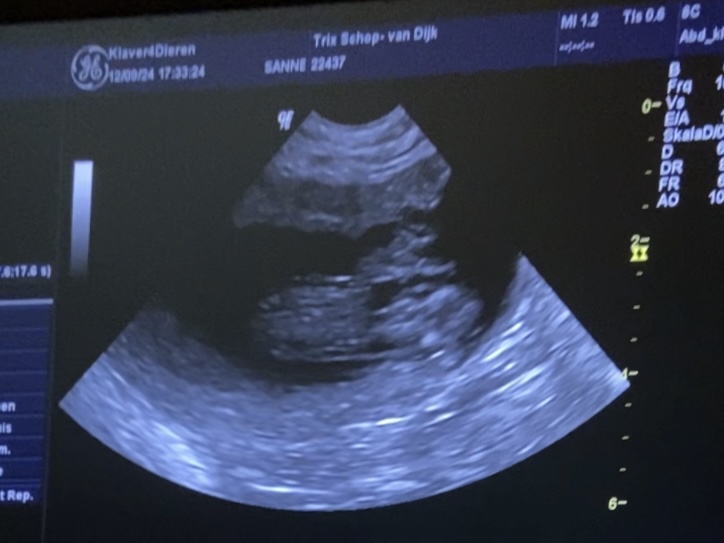

12-9-2024 Op deze dag zijn wij uiterst nerveus naar de Dierenarts gereden. Hoewel je gevoel zegt dat het wel goed zit, wil je het toch zeker weten. In eerste instantie leek Trix niet heel erg gegroeid, maar toch bleek ze al bijna 5 kilo te zijn aangekomen. Voorzichtig is onze dierenarts met de scan over haar buik gegaan. Helaas vraagt het precisie werk en kon er niet met 100% zekerheid gezegd worden hoeveel pups Trix draagt. Maar dat ze dracht is = 100%